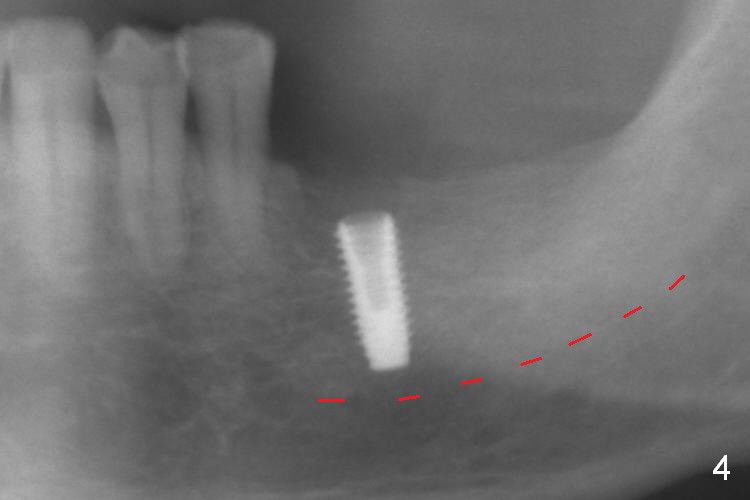

As indicated by CBCT, the ridge at the site of #19 is pointed (Fig.1). After regional ridge reduction (Fig.2) and use of 2 mm pilot drill for 8.5 mm, the depth is actually ~ 10 mm. After sequential osteotomy until 4.3x10 mm drill, the osteotomy is in fact 11.5 mm deep; a 5x11.5 mm implant is placed with <35 Ncm (Fig.3). Panoramic X-ray shows the implant close to the superior border of the Inferior Alveolar Canal (Fig.4 red dashed line). The ridge looks wider and more bulging (*) when a 6.5x5.5(5) mm abutment, allograft/Osteogen and Osteotape (GBR) are placed (Fig.5 (lingual) and 6 (buccal)). Periodontal dressing is then applied. There is no postop paresthesia. The abutment dislodges 3 weeks postop. A healing abutment is placed (6.5x4 mm). The patient returns for restoration 4 months postop; bone density appears to increase around the implant (Fig.7 arrowheads). When a 7.5x5(4) mm abutment is placed, there is transient pressure on the gingiva (blanching). The mesial gingival trough is formed by Diode laser prior to impression.